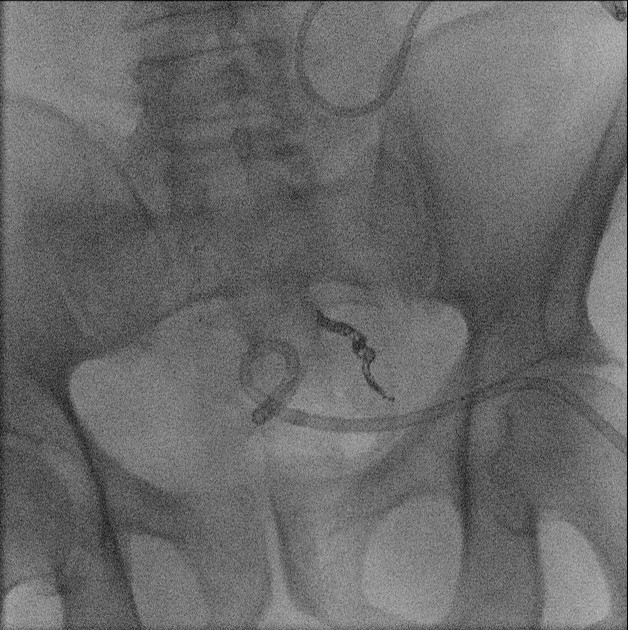

- Upon entering the room, the patient will already be positioned supine on the fluoroscopy table. The interventional portion of the exam is performed by the Gynecology Department; the cervix should be cannulated and a catheter placed when you enter the room.

- Introduce yourself to the patient and the staff in the room.

- Move the fluoroscopy tower over the patient centering on the pelvis.

- The gynecologist will begin injecting contrast material into the uterus. Obtain images periodically throughout the procedure (usually at the direction of the gynecologist). The images should include the uterine cavity filled with contrast material, bilateral fallopian tubes filled with contrast material, and spillage and dispersion of contrast material into the peritoneal cavity (image 1) (image 2) (image 3) (image 4) (image 5).

- It may be necessary to place the patient into either the right lateral or left lateral oblique postion to define the anatomy more clearly.

- Spillage into the peritoneal cavity is not always seen. If this occurs during the examination, be sure to note it in the dictation.